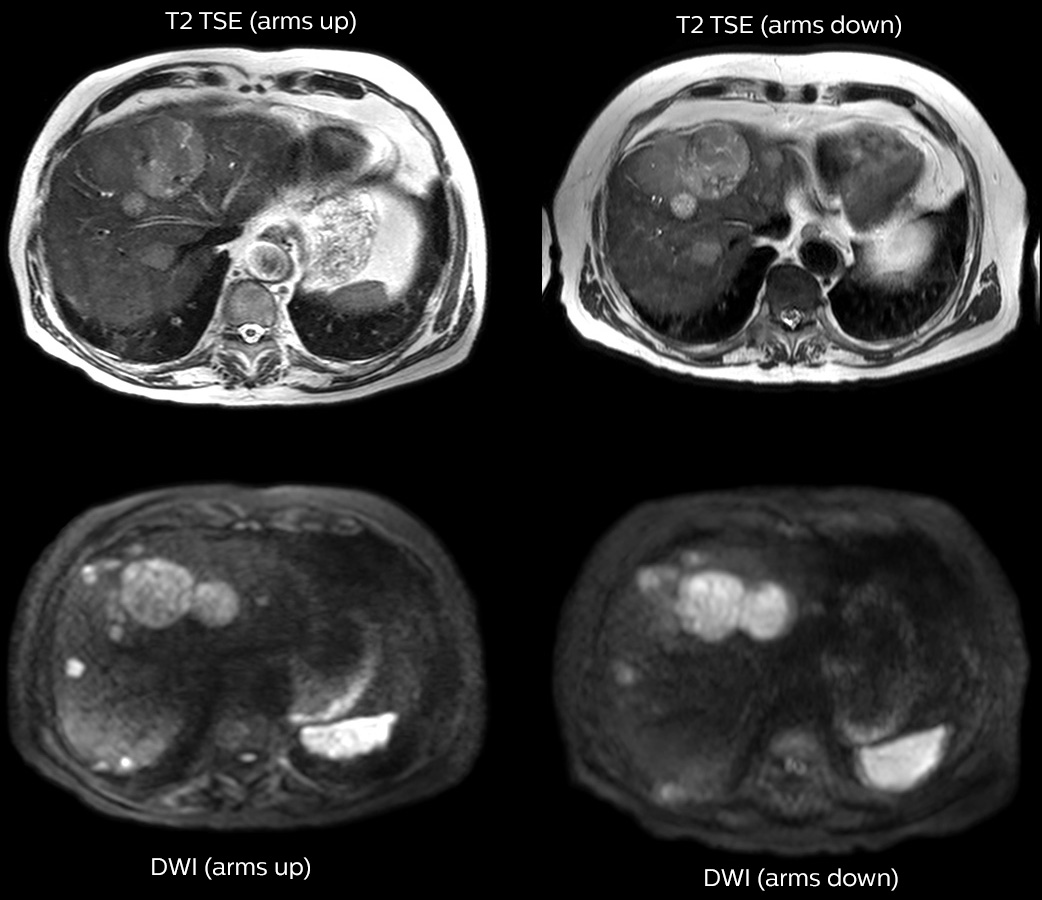

Imaging with arms up means faster, better imaging

Dr. Kukuk scans an increasing number of liver patients in an arms-up position using the integrated Posterior coil and a special positioning device. “By placing the patient’s arms up, the field of view in the right-left direction can be smaller so that a right-left preparation direction can be used to cut down the scan time,” he explains. “We can use high dS SENSE factors for TSE imaging, so we can shorten the echo train length. This results in a faster scan than arms-down T2 TSE and the images show high anatomical detail.”

“For DWI, the high dS SENSE factor allows using a shorter TE so we get higher signal and fewer susceptibility artifacts, which means less distortion of diffusion weighted images. Of course, with higher dS SENSE factors and the shortening of the TSE factor in T2-weighted imaging, we can drastically cut down the complete examination time. So, with arms-up we get faster images, less distortion in DWI and less blurring on T2-weighted images. Almost all patients tolerate the arms-up scanning well.”